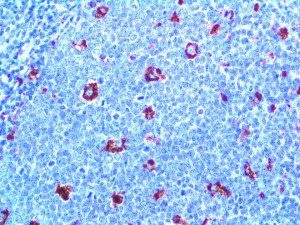

It is the ICU physician who is most likely to witness one of the deadliest manifestations of the abnormal immunological response, the cytokine storm syndrome (CSS). This response is also referred to by some as the cytokine release syndrome (CRS). CSS is characterized by continuous activation and expansion of macrophage and lymphocyte populations, which secrete large amounts of cytokines, causing the cytokine storm. This massive cytokine release is akin to hemophagocytic lymphohistiocytosis (HLH) disease, a syndrome characterized by initial unchecked and persistent activation of cytotoxic T lymphocytes and NK cells.

Clinical and laboratory manifestations of HLH include fever, enlarged liver and/or spleen, neurologic dysfunction, coagulopathy, liver dysfunction, cytopenias (i.e., low levels of erythrocytes, leukocytes, and/or platelets), hypertriglyceridemia, hyperferritinemia, hemophagocytosis, and eventually diminished NK cell activity as the immune system becomes progressively paralyzed. HLH can be familial (primary HLH) or secondary to another disease process (sHLH), such as rheumatic disease, in which it is referred to as macrophage activation syndrome (MAS, characterized by elevated ferritin).